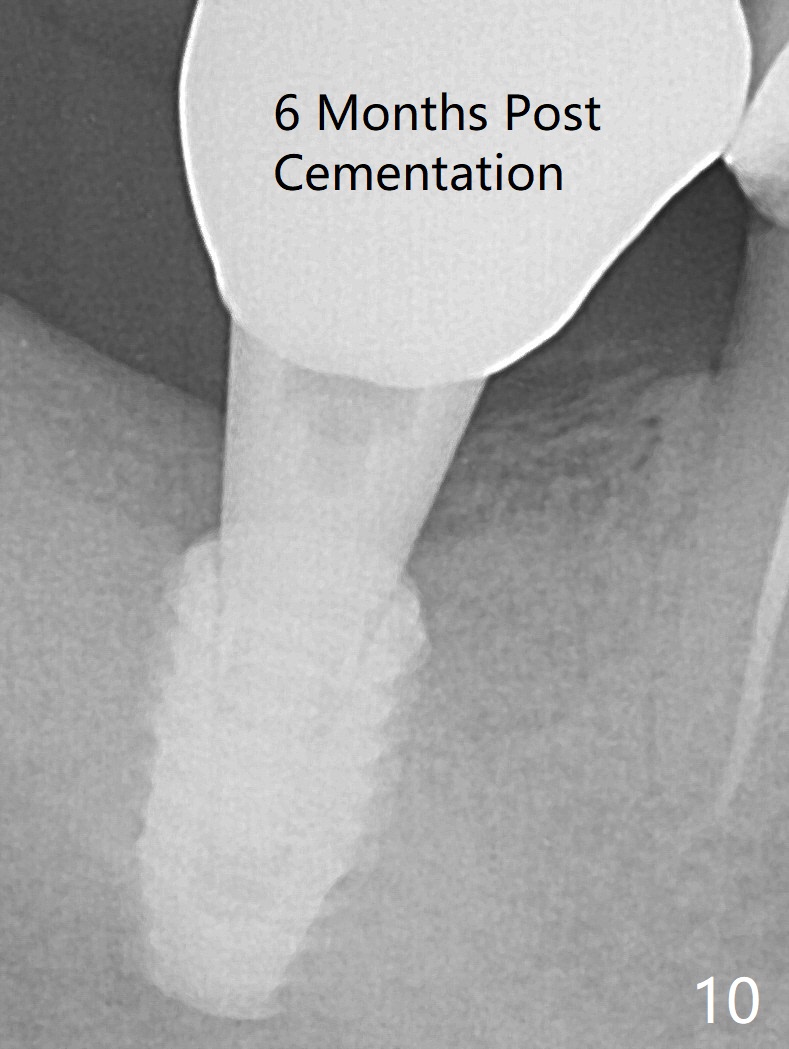

The trajectory is not right, since no matter how the sensors are placed, the implant threads cannot be shown clearly (Fig.10), in consistence with the distolingual access hole (Fig.11).